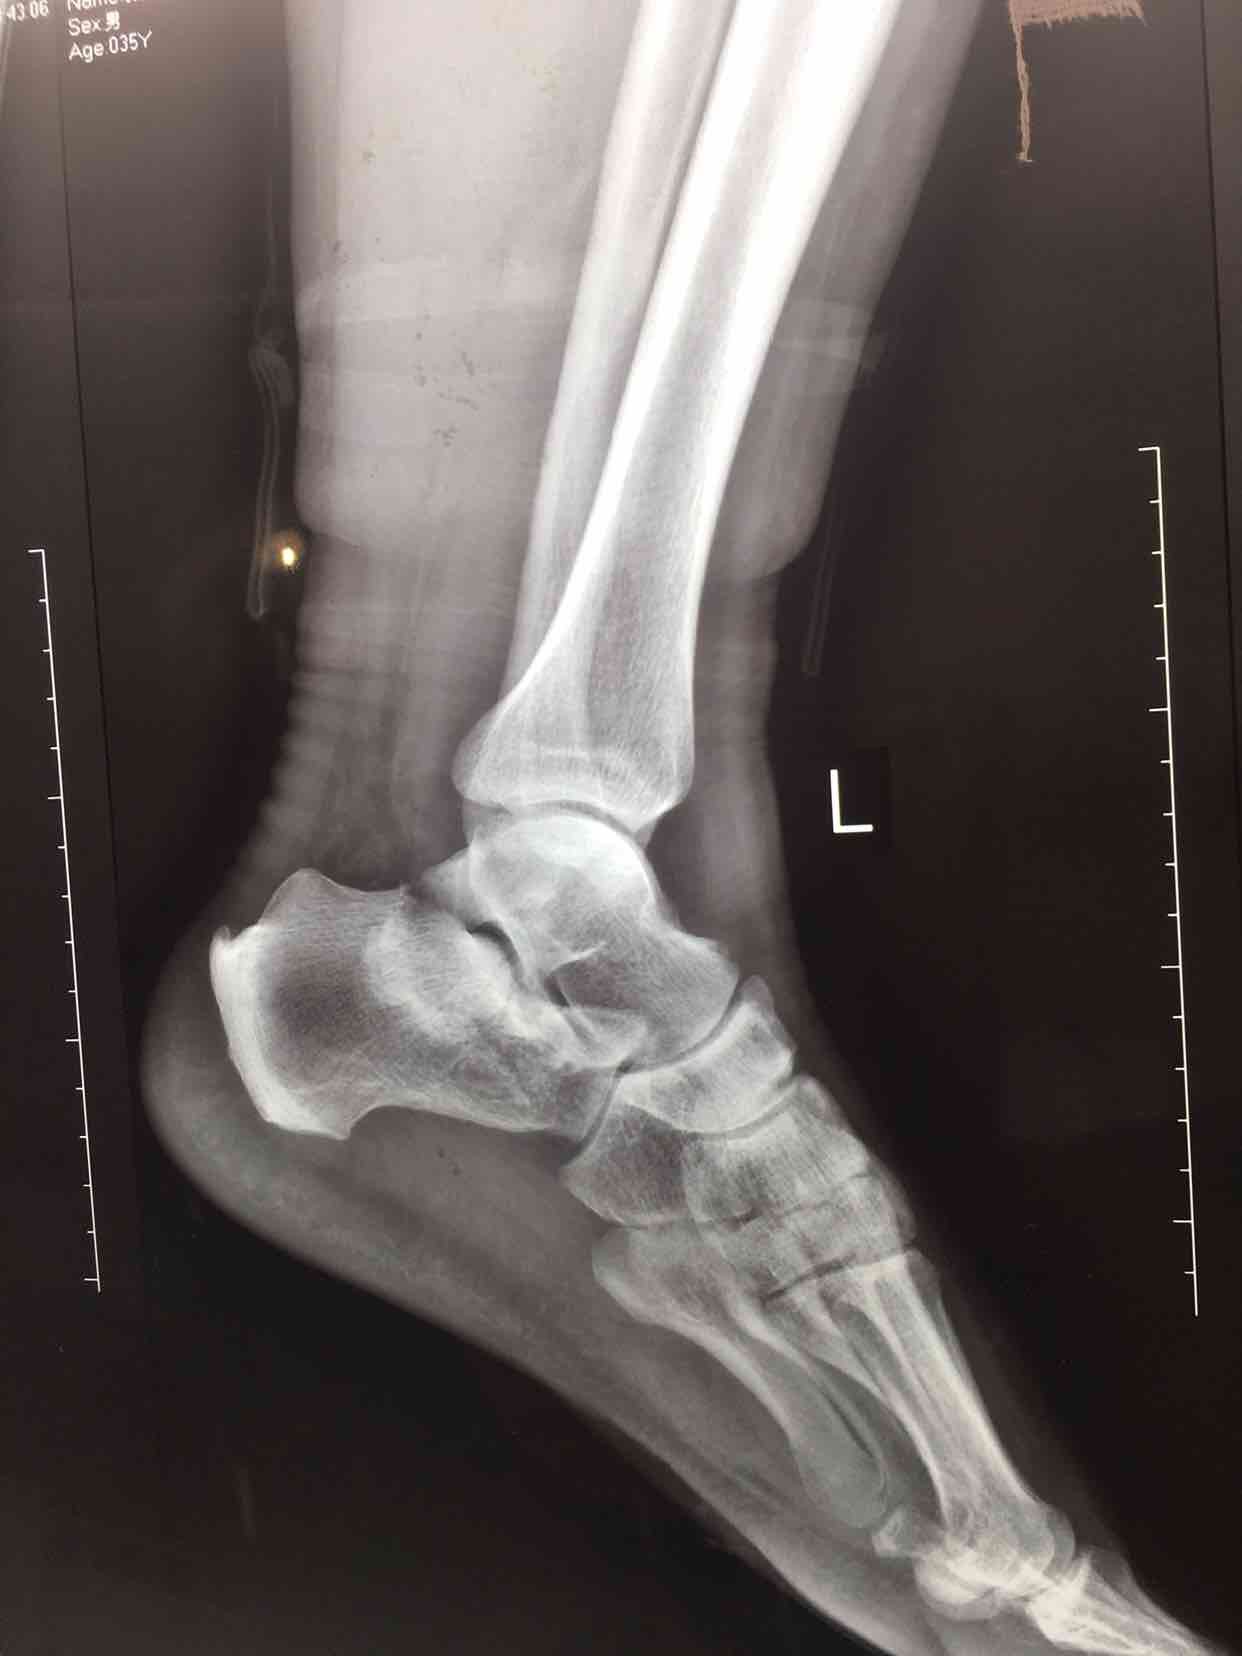

摔伤后左足肿痛,活动受限1小时入院。既往身体健康,体重95公斤,有吸烟史10年,无其他特殊不良嗜好

生命体征平稳,心肺复未见异常。左足肿胀明显,局部皮色发红,皮温高,压痛及纵向叩击痛阳性,末梢血运感觉正常。

诊断  左跟骨粉碎性骨折完善术前检查,在腰麻下行切复内固定术,术中撬拨复位,选用克氏针临时固定,放置锁定钛板固定,术后抗炎,消肿等处理。